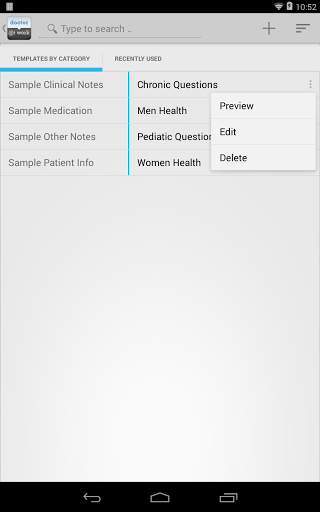

• Outil puissant intégré pour aider à gérer les notes réutilisables